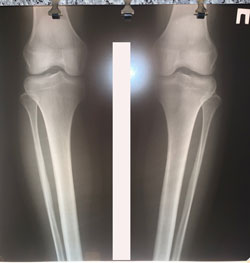

Исходник - 24 года.

Дата операции - 01.12.2020

Варусная деформация голеней + Ротация с обеих сторон